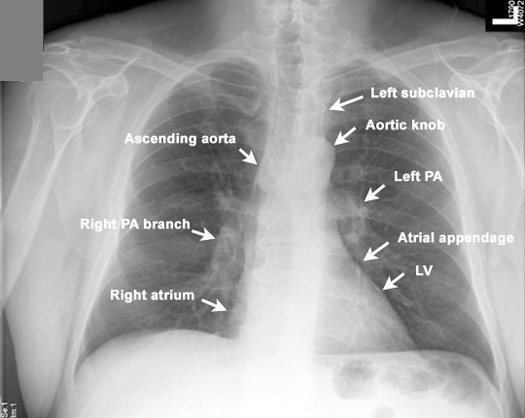

Identify the structures along the edge of the mediastinum. Click the image for labeling.